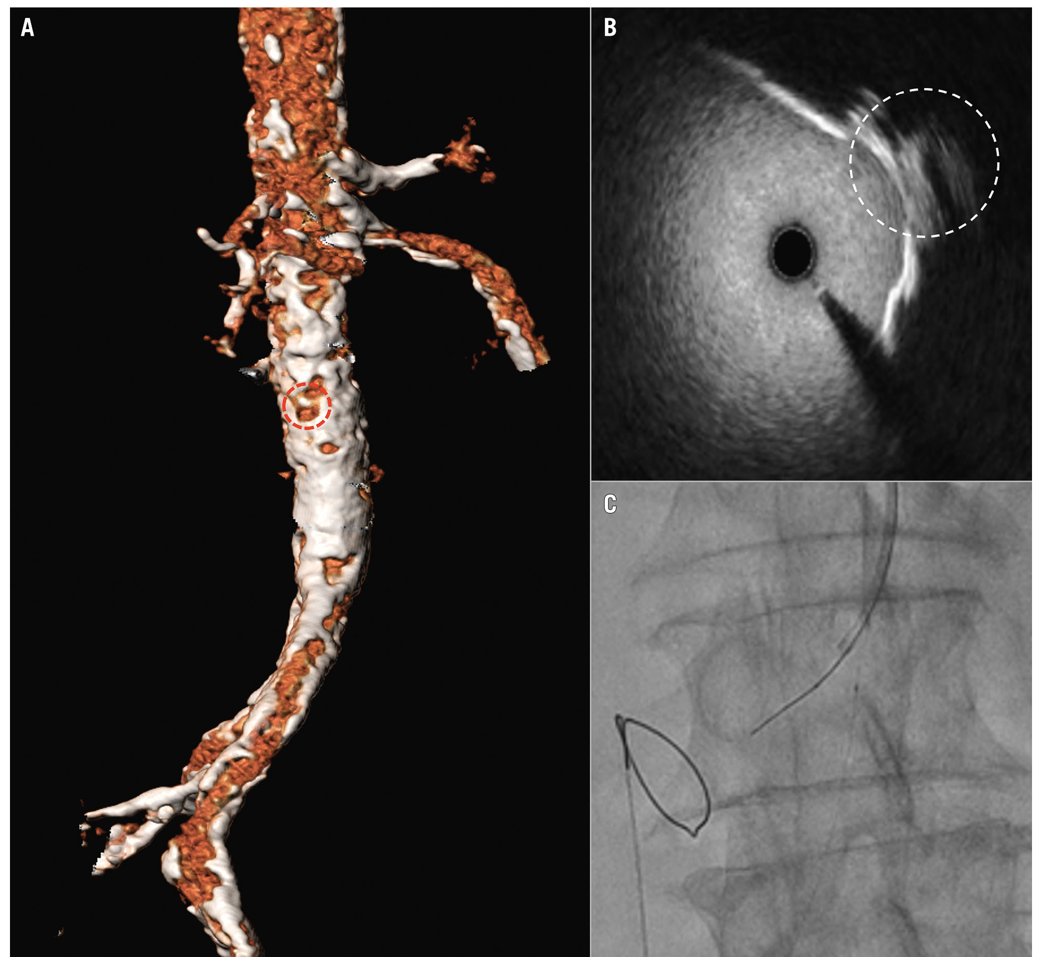

When transfemoral access is not feasible for #TAVI, transcaval access may offer a solution. This case showed a modified #transcaval approach using IVUS to navigate severe aortic calcification, enabling safe valve delivery in a high-risk patient. ow.ly/1O1l50W75hh #EAPCI

When transfemoral access is not feasible for #TAVI, transcaval access may offer a solution.

This case showed a modified #transcaval approach using IVUS to navigate severe aortic calcification, enabling safe valve delivery in a high-risk patient.